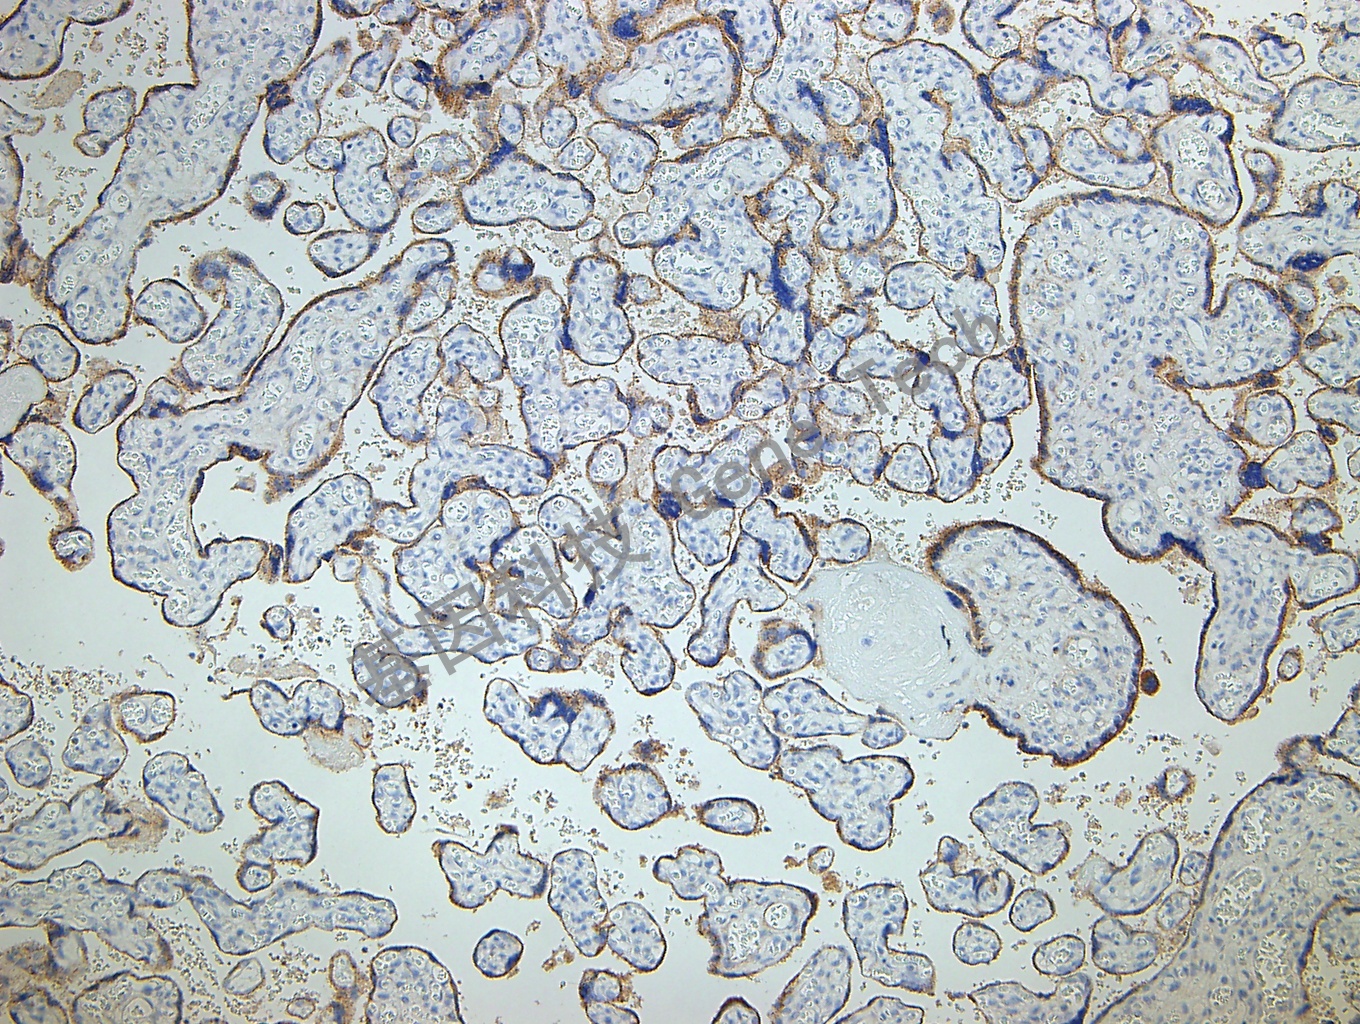

胎盘石蜡切片,用 Glypican-3(GT2068)染色,细胞膜/细胞浆阳性,DAB 显色。